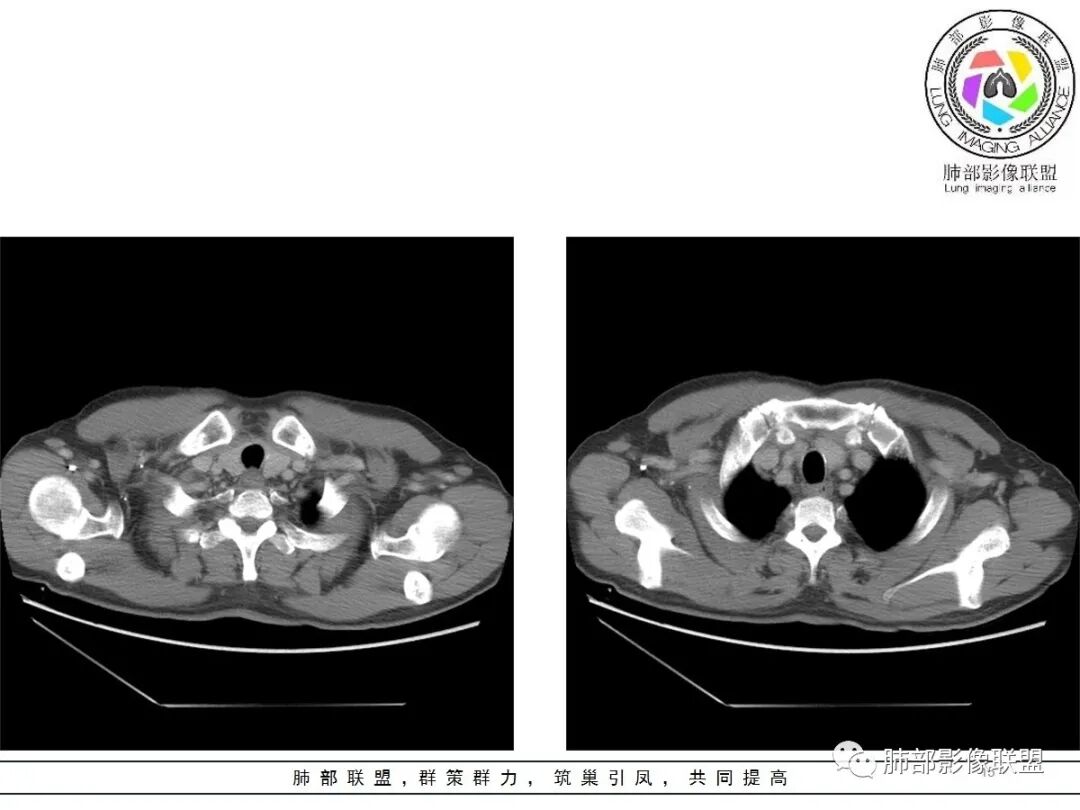

大雄:老年男性  急性起病 胸痛1天前纵隔占位伴右侧少量胸水,肿块整体膨隆,密度不均匀,可见坏死,纵隔脂肪间隙模糊不清常规考虑胸腺瘤/癌并梗死

一切∮随缘:定位肺外,病变位于右前纵隔,与肺部交接面清晰,有胸膜尾征,心包局部受压,部分包绕主动脉血管,平扫密度均匀,形态规则,膨胀性生长,增强扫描壁有强化,内容物无明显强化,考虑1:淋巴瘤2:胸腺瘤3:神经鞘瘤4:支气管囊肿

亚东:前纵隔囊实性肿物,形态尚规则 ,与心包分界不清,内可见小气泡,嚢内平扫密度低,强化不明显,囊壁强化,右胸腔积液,淋巴结肿大不明显,化验白细胞高,支持囊肿伴感染。

小强:前纵隔肿块,边缘模糊,其内有点状气体影,环形强化(肉芽肿?),心包胸膜受累,疾病谱:胸腺瘤(一般是侵袭性胸腺瘤累计心包,胸膜,强化不符合)淋巴瘤,生殖细胞瘤(年龄,AFP不高不负),考虑畸胎瘤,囊性畸胎瘤合并感染,边缘模糊,累计心包胸膜,3.19病变进展,胸腔积液,可能有破溃

采莲:老年男性,胸疼病史,右上前纵隔肿块,边缘光滑,平扫内部密度稍均匀,轻度强化,内有低密度区,与支气管关系不大,右侧少量积液。考虑来源纵隔,老年男性,胸腺瘤或胸腺癌,鉴别淋巴瘤。

冥冥之中:定位,右前纵隔

定性,肿块边缘模糊,右侧胸腔积液,上腔静脉边缘侵袭,恶性

年龄68常规考虑胸腺癌,但是里面有脂肪成分,周边有钙化,畸胎瘤不能排除

综合考虑,前纵隔恶性病变,畸胎瘤>胸腺癌

廖鹏飞:定位右前上纵隔没问题吧

廖鹏飞:可疑胸腺动脉进入肿块

廖鹏飞:考虑胸腺瘤合并感染,畸胎瘤待排

修*:前纵隔偏右侧肿物,点状钙化,轻度强化,伴胸腔积液,考虑胸腺瘤B2型。

岁月:男性,68岁,右胸痛一天,无家族史,右上中叶纵膈旁占位;抽烟50年,3天1包。wbc高。与纵膈脂肪间隙不清,胸水,快进快出 分叶,有血管样强化,9.1-11.4-10.9。诊断:错构瘤,似乎都符合;但如果恶性放在前面,肉瘤、恶性。鉴别:错构瘤、侵袭性胸腺瘤;处理:经皮肺活检、手术。

王秀仙:右侧前纵膈肿块,密度不均,局部边缘可见点状钙化,其内可见点状低密度,与纵膈血管间脂肪间隙消失模糊,右侧胸腔积液,考虑纵膈畸胎瘤或皮样囊肿破裂。鉴别胸腺鳞癌。

必有路:老年人,右前纵隔占位,发病前纵隔脂肪干净,突发起病伴胸痛,白细胞增高病灶整体密度较为均匀,内有点状脂肪密度,位置个人觉得理胸腺区有点偏下,大部分囊性为主1、胸腺瘤伴突发梗死  突发起病,老年男,不支持点,位置偏下,囊变坏死太彻底,右侧胸廓内动脉没有增粗(实性肿瘤,往往会有间接供血增粗)倾向支持囊性病灶合并破溃感染2、囊性畸胎瘤伴破溃  影像上可以支持,脂肪含量比较少,发病年龄不太支持3、 皮样囊肿 可以有脂肪密度4、 支气管囊肿 理论上胸廓内都可以发生,肺内 后纵隔多见 张力大 圆5、心包囊肿  中纵隔更为多见综上,皮样囊肿>囊性畸胎瘤>胸腺瘤